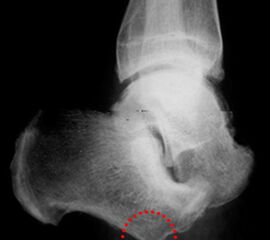

Der kraniale Calcaneus wird so mit der oszillierenden Säge reseziert, dass bei der Fusion mit der Tibia die physiologische Inklination von 30° wieder hergestellt wird (Abb. 48). Wird der Calcaneus zu steil eingestellt, kann das zu erhöhter Druckbelastung am Tuber calcanei und damit zur Ulzeration führen. Eine flache Einstellung des Talus wird von manchen Operateu­ren bevorzugt. Dies ist technisch vielleicht etwas einfacher, führt jedoch zu einer stärkeren Verkürzung. Varus- und Valgusfehlstellungen müssen vermieden werden.

Zur Osteosynthese bevorzugen wir 2-3 kanülierte Großfragmentschrauben (Abb. 49). Postoperativ ist die Extremität für 8 Wochen zu entlasten, wobei zur Sicherheit eine Entlas­tungsorthese verordnet werden kann. Bei schwachen oder unzuverlässigen Patienten empfiehlt es sich, für 8 Wochen einen Ring-Fixateur anzulegen.